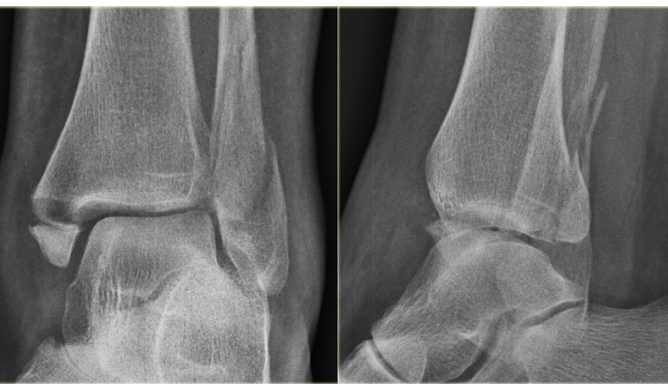

6

abnormality

A

minimally displaced fracture distal tibia with intra articular involvement

8

list abnormalities

diagnosis

management?

• medial mallolar fracture

• posterior tibial fracture

• fibula fracture

• lateral talar displacement

*

unstable tri malleolar fracture*

management

* analgesia - state

* sedation

* below knee backslaab

* elevation

* ortho admit for ORIF